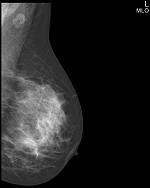

Метод прицельной маммографии с увеличением применяется для более детального исследования определенной области молочной железы. Он отличается высокой точностью диагностики. В отличие от обычной маммографии, которая предоставляет более общую информацию о состоянии молочных желез, прицельная маммография с увеличением позволяет получить точные данные о процессах, происходящих в тканях, благодаря методу компрессии конкретного участка.